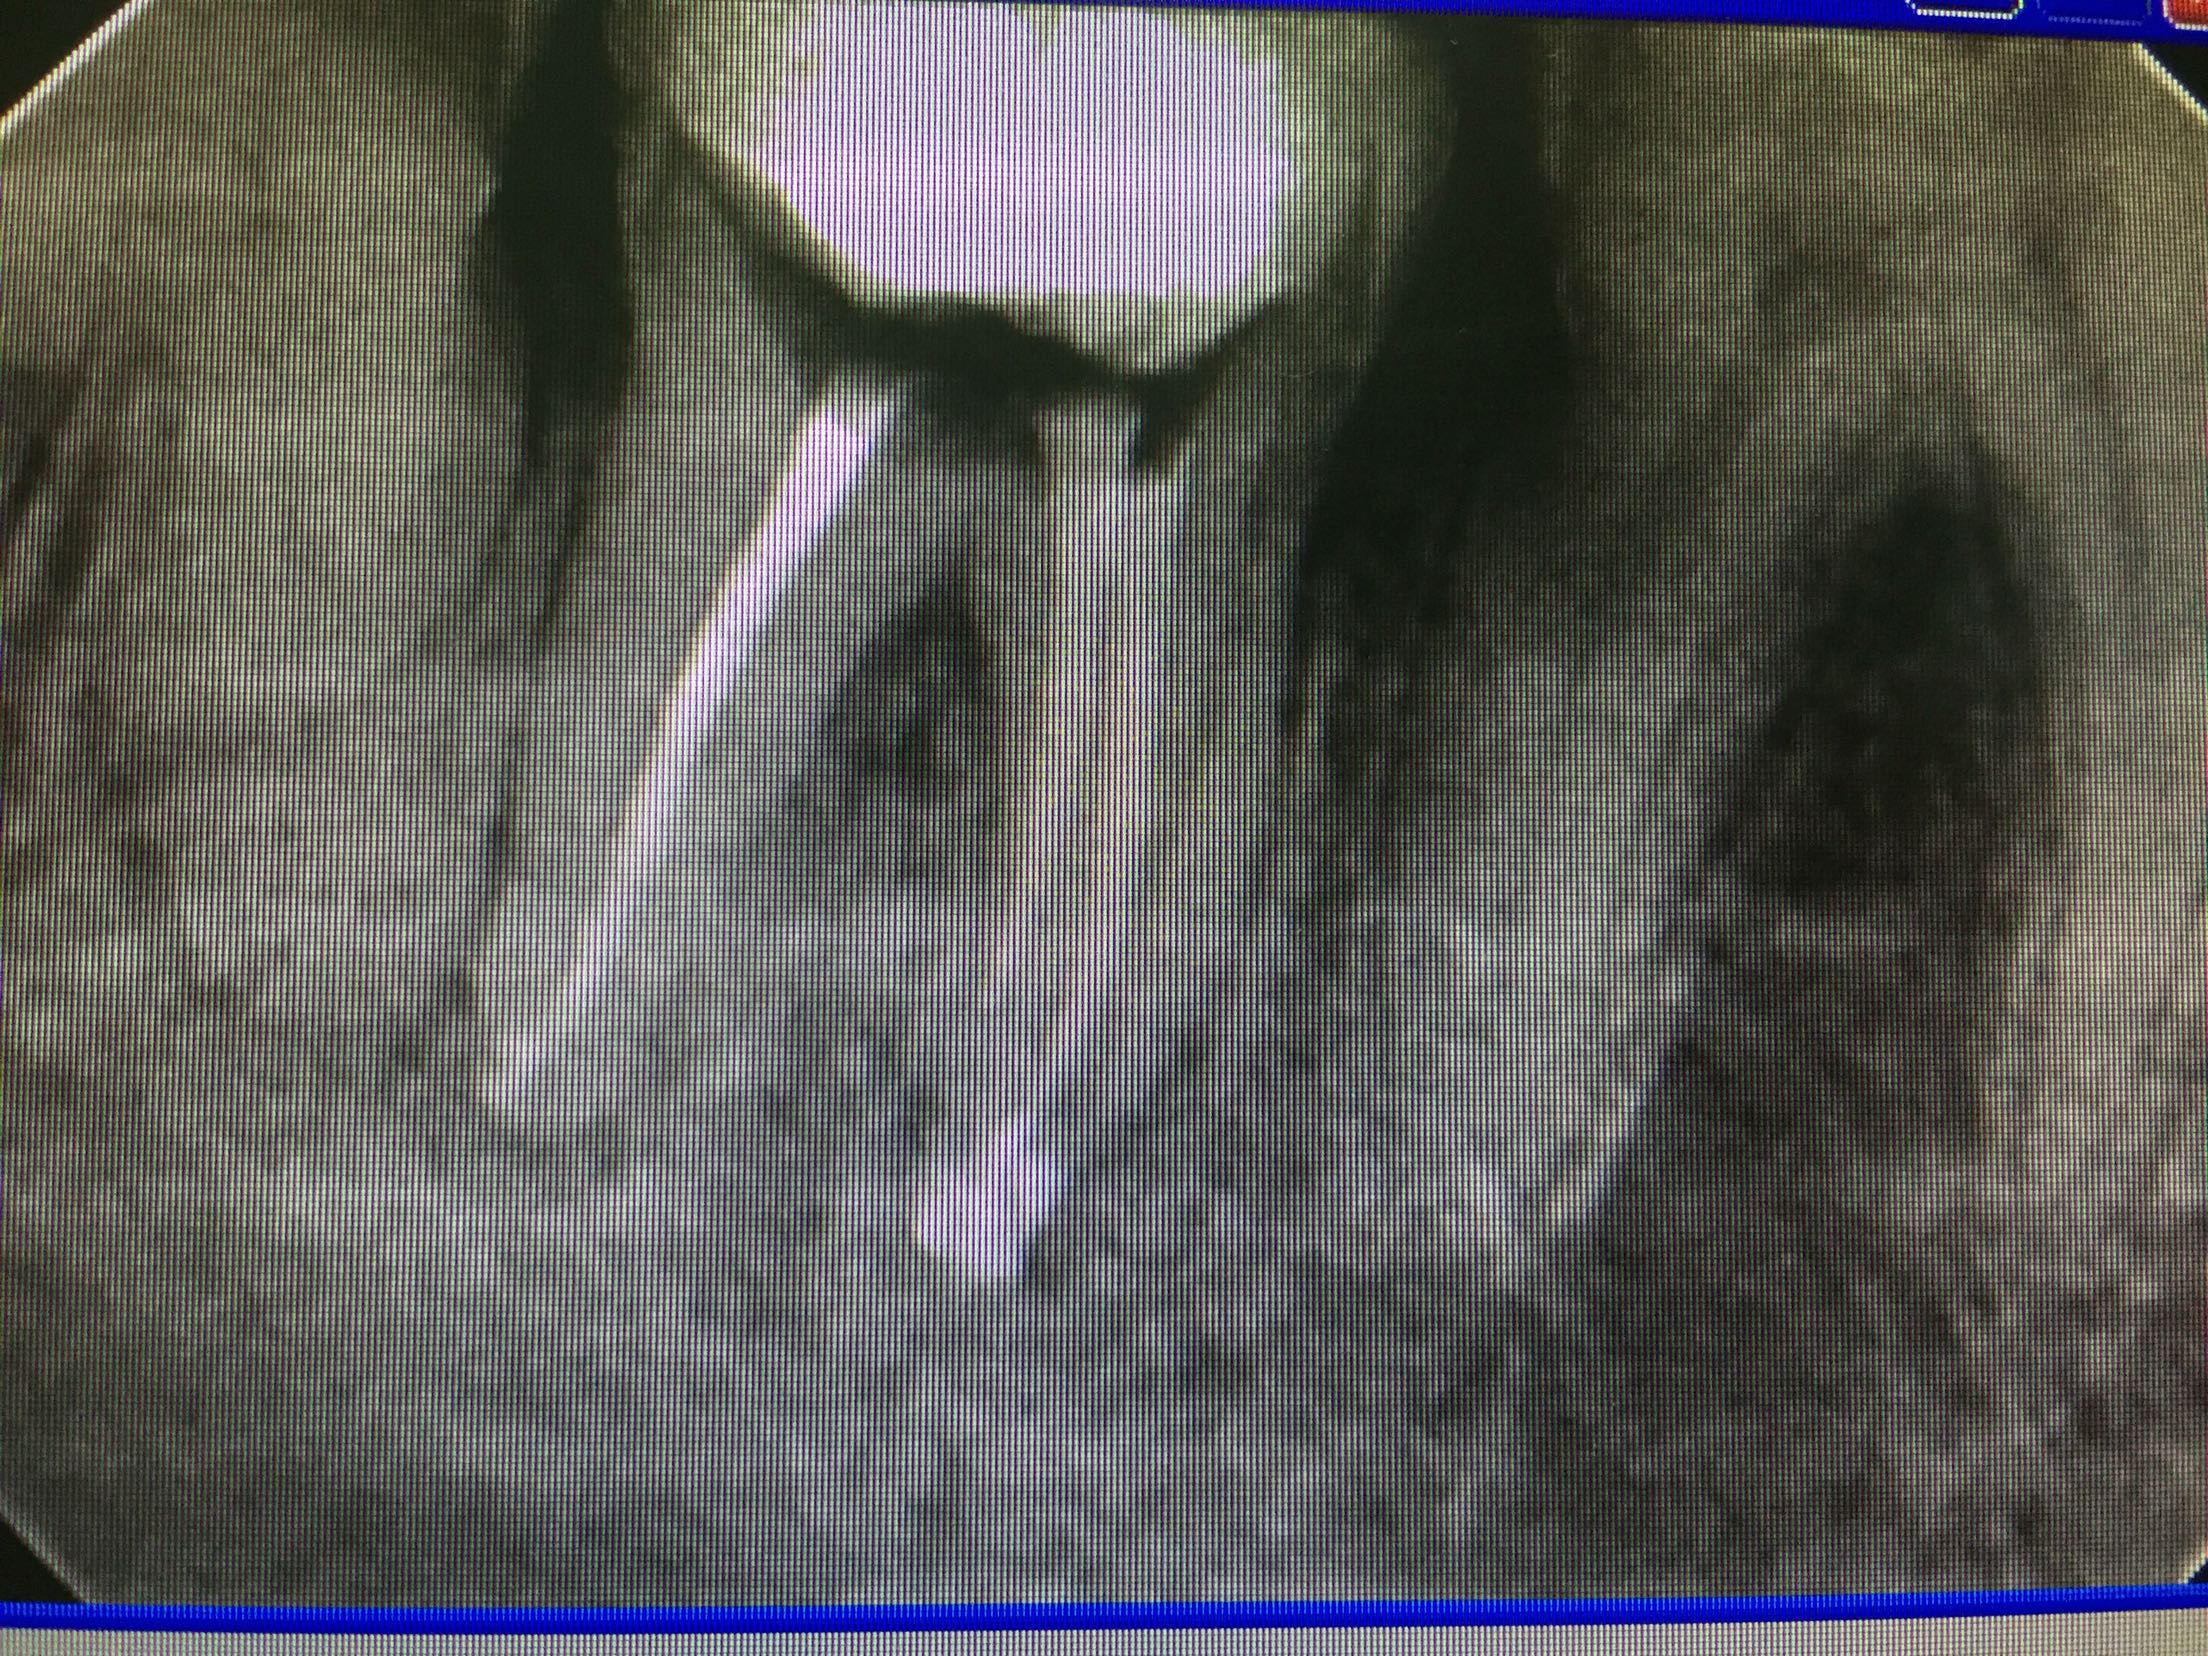

检查:47颊合面深龋,探及穿髓,探痛无,牙龈未见明显红肿,冷诊(-)。X线片示:47根尖区低密度影像。

诊断:47慢性根尖周炎 治疗:47去龋净,开髓揭顶全,拔髓,疏通根管,测长,根管预备,冲洗,干燥,试尖,根管封药,告医嘱,肿痛随意。